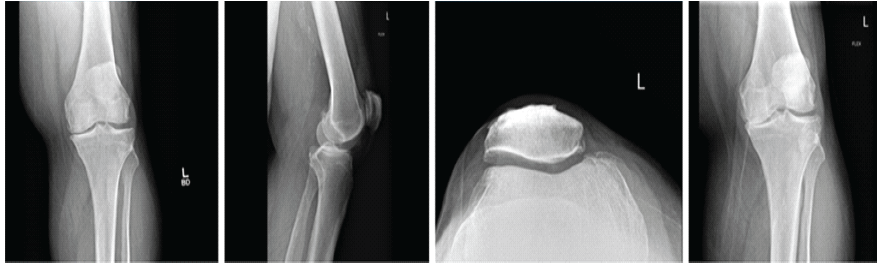

A 58-year-old white male with a past medical history of obesity, diabetes, and hypertension presented to the clinic with complaints of severe left knee pain with ambulation. The patient presents with a morbidly obese body habitus, weighing 345 lbs with a height of six feet (body mass index [BMI] 46.8). He is a non-smoker and occasionally drinks alcohol. He also reports exercising on occasion. The patient attempted and failed conservative treatment up until this point. He reports working as a maintenance man, where he bends and kneels for long periods of time daily. The patient underwent X-ray imaging, which included four views of the left knee, including anteroposterior (AP), lateral, patellofemoral, and tunnel views. The imaging provided clear advanced osteoarthritis with bone-on-bone articulation of the medial component of the knee and varus alignment (Fig. 1).

Figure 1: Pre-operative X-rays. Four views of the left knee are visualized on the patient’s initial visit, including anteroposterior, lateral, patellofemoral, and tunnel views, respectively. Bone-on-bone articulation of the medial component of the knee is appreciated.